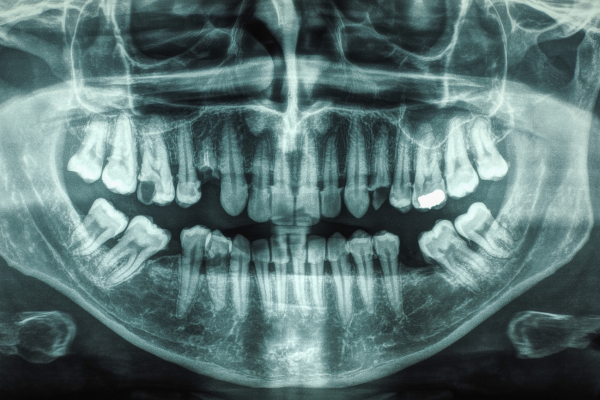

Dental Radiography Gives the Whole Picture

There is only so much we can see without X-rays!

Dental X-ray of a human mouth

Panoramic – A panoramic view X-ray shows all the upper and lower teeth, large portions of the jaws and other structures in one large picture. It is often used to find unerupted teeth, cysts, fractures, retained root fragments, and other conditions of the jaw. It does not generally show enough detail to be useful for detection of decay and bone loss from periodontal disease.